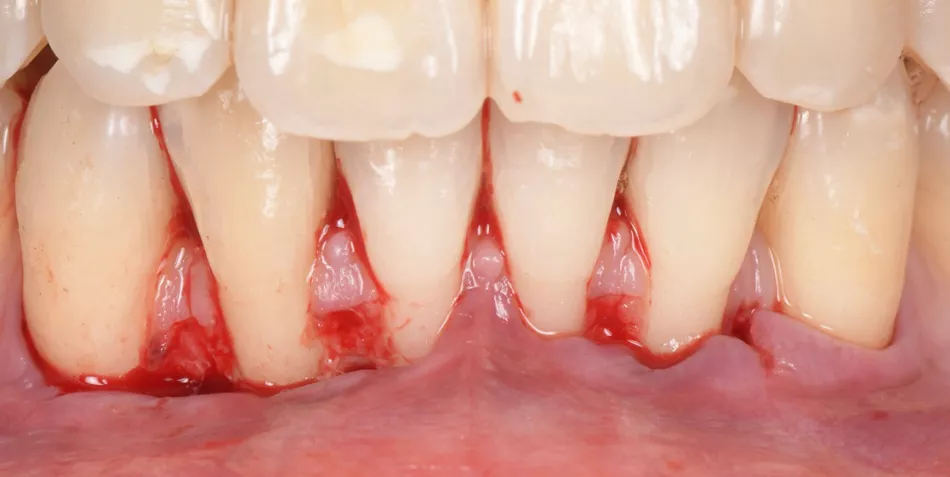

A 35-year-old female, healthy (ASA I), non-smoker, with no medication, came to our practice complaining about gingival recession and pain while brushing her mandibular incisors.

The intraoral examination revealed multiple RT 1 (Cairo 2011) gingival recessions on teeth #33 to #43, along with a thin tissue phenotype, which was associated with a traumatic toothbrushing habit (Fig. 1).